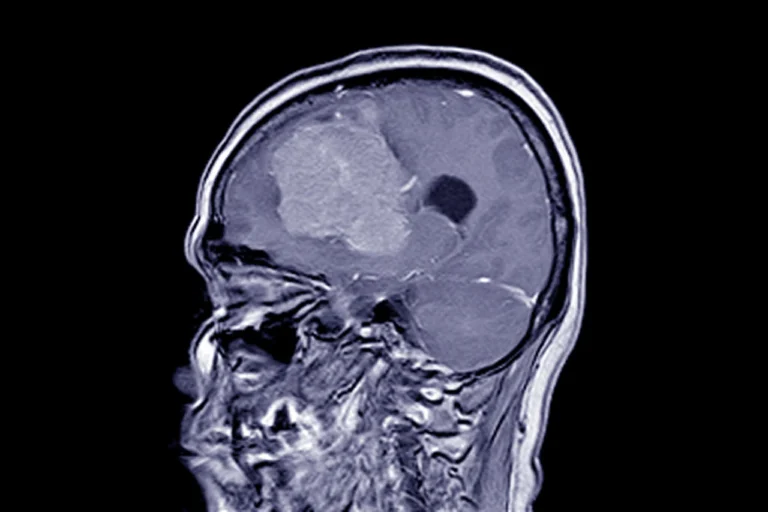

Менінгіома — це пухлина, що розвивається з оболонок головного мозку. Вона може бути доброякісною або злоякісною, але навіть у разі успішного видалення пацієнта чекає непростий період відновлення. Багато хто цікавиться, скільки триває реабілітація після такої операції і які етапи вона включає. Детальніше про це, а також про можливі наслідки після хірургічного втручання, можна дізнатися на […]